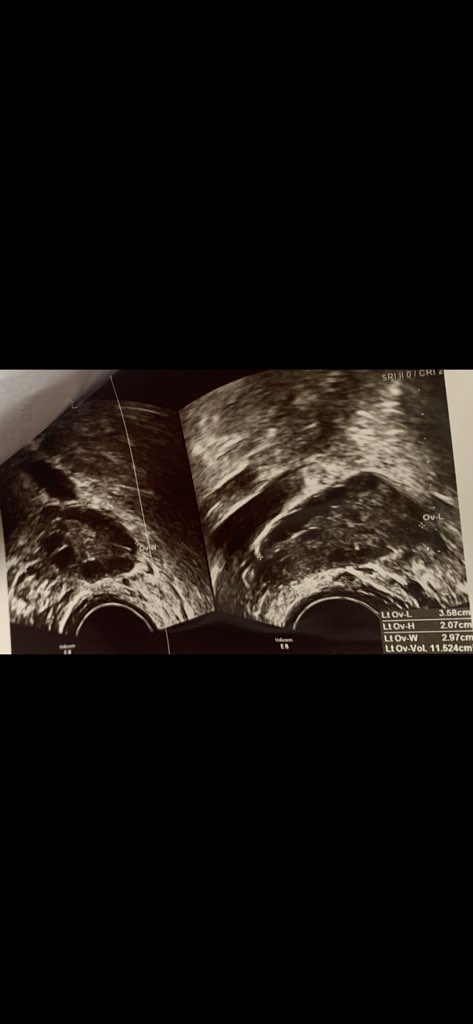

DawajJeśli nie macie nic przeciwko to wrzucę tu zdjęcie z USG i zobaczycie. Mogę wrzucić, czy wolicie na to nie patrzeć?

Uwierz jak Ci wszytskie mówimy. Na jednym masz pęcherzyk 14mm a na drugim 18mm.2 pęcherzyki to super. Może pękną oba. Ale dominujący jest ten 18mm i pewnie on pęknie. Rezerwy nie zobaczy lekarz bo te pęcherzyki nie rosną sobie jak czereśnie i nie pękają prosto z "gałęzi"Już więcej nie czytam nic w internecie, bo tylko głupsza się robię![]()

Uwierz jak Ci wszytskie mówimy. Na jednym masz pęcherzyk 14mm a na drugim 18mm.2 pęcherzyki to super. Może pękną oba. Ale dominujący jest ten 18mm i pewnie on pęknie. Rezerwy nie zobaczy lekarz bo te pęcherzyki nie rosną sobie jak czereśnie i nie pękają prosto z "gałęzi". Jeśli miała byś taka małą rezerwę to zostałoby Ci 32 cykle płodne, a później menopauza

To po prawej to wieloryb!!! Zgadłam!?Tak to wyglada![]()